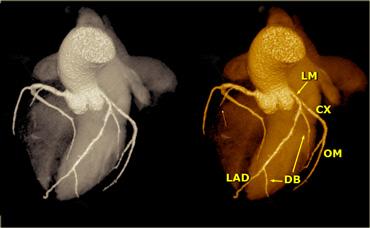

Trên hình bên trái, chúng ta thấy thân chung động mạch vành trái phân chia thành

- Cx với nhánh bờ tù (OM)

- LAD với các nhánh chéo (DB)

Trên các hình ảnh dựng hình thể tích (volume rendered), cần loại bỏ tiểu nhĩ trái để quan sát rõ LCA.